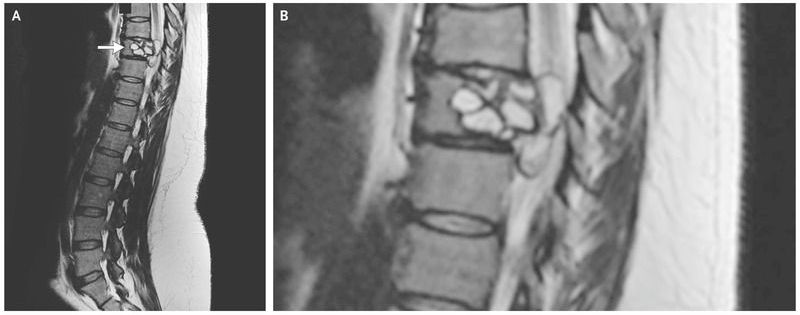

A 35-year-old woman presented to the emergency department with weakness, a feeling of electric shocks in both legs, and repeated falls. She reported that the symptoms had been progressing, and she noted that she had had difficulty riding her horse for the preceding 3 months. She lived in France, had no history of foreign travel, owned a pet cat, and had contact with cattle. Physical examination revealed impaired sensation in both legs and weak foot flexion. Laboratory tests showed an elevated total white-cell count (18,800 per cubic millimeter; reference range, 4000 to 10,000) with a normal absolute eosinophil count and a C-reactive protein level of 49 mg per liter (reference value, <5). Magnetic resonance imaging of the spine revealed a lobulated lesion of the 9th thoracic vertebra with an epidural component (Panel A, arrow; a close-up image is shown in Panel B). Surgical treatment involved posterior corpectomy of the 9th thoracic vertebra, osteosynthesis of the 7th through 11th thoracic vertebrae, and removal of the epidural lesion. Pathological testing revealed cystic echinococcosis (hydatidosis), and reverse-transcriptase–polymerase-chain-reaction assay identified Echinococcus granulosus. Echinococcus is a parasitic cestode that can infect dogs and other pets and farm animals, with humans as incidental hosts. Infection can cause cystic lesions in the liver and lungs and also in the central nervous system and bones. In addition to surgery, this patient was treated with the antiparasitic medication albendazole. At follow-up 9 months after presentation, the patient had no residual symptoms or sign of recurrence.